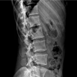

X-RAY Áø´Ü

ȯÀÚÀÇ ½Åü »óÅÂ¿Í ÅëÁõ ºÎÀ§ ¹×

ÇöÀç ¹®Á¦Á¡ µîÀ» ÆÄ¾ÇÇϱâ À§ÇØ

X-RAY ÃÔ¿µÀ» ÇÕ´Ï´Ù.